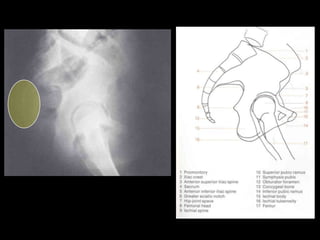

This document provides an overview of normal musculoskeletal imaging. It discusses basic x-ray concepts and densities. It then reviews normal anatomy as seen on x-rays of the skull, spine, pelvis, chest, and extremities. Key anatomical structures are labeled on example x-rays for the shoulder, hip, knee, and foot. Quizzes are included to test recognition of anatomical structures and patient age based on x-rays.